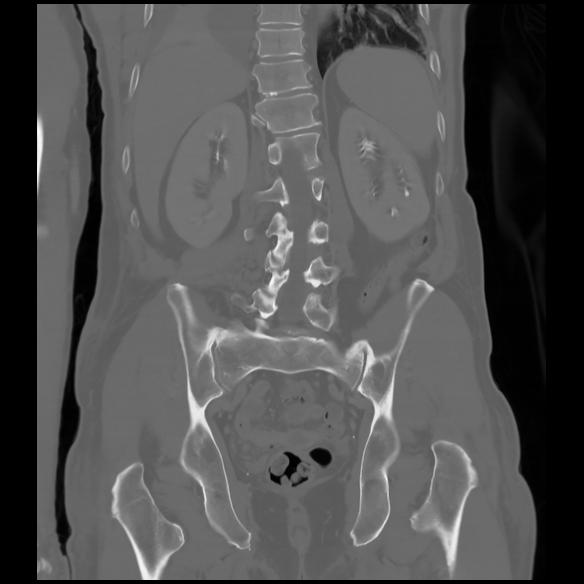

6 CUERPO,CE,Coronal,3.000,CUERPO,Coronal,